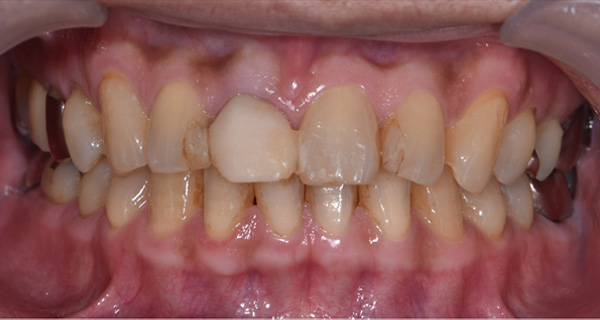

BEFORE

| 年代・性別 | 50代 男性 |

|---|---|

| 主訴 | 右上下の歯が痛い |

| 治療期間 | 約12ヶ月 |

| 費用 | 2,500,000円 |

| 治療内容 | インプラント、骨造成、結合組織移植、セラミック修復 |

| 治療に伴うリスク | インプラント周囲炎 セラミックの破折、脱離 |